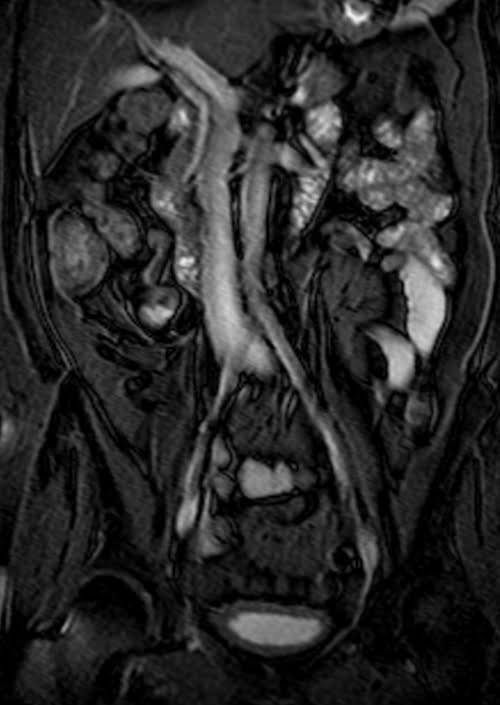

MRI kidney ureters and bladder( KUB) T2 TrueFISP fat saturated coronal images